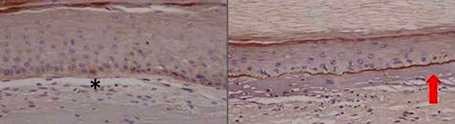

Edición genómica para la epidermólisis bullosa: un poco más cerca de la clínica

Edición genómica para la epidermólisis bullosa: un poco más cerca de la clínica La epidermólisis bullosa distrófica recesiva o piel de mariposa es una enfermedad rara de fragilidad...